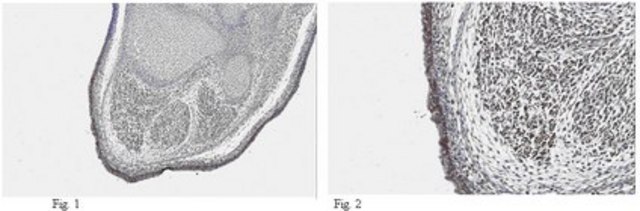

Immunohistochemistry Analysis: A 1:1,000 dilution from a representative lot detected DLK1 in mouse embryonic tissue.